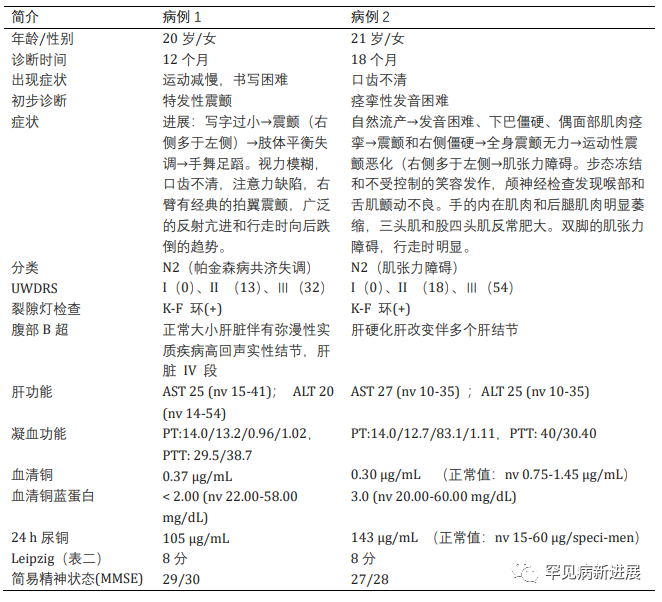

病例情况 病例一:伴有帕金森症状的共济失调型;病例二:伴有帕金森症状的肌张力障碍。两名患者均接受裂隙灯检查有 K-F 环(图1)。 肝脏超声检查有明显结构异常,实验室检查肝功能正常,低血清铜、低铜蓝蛋白和尿铜排泄增加,均无基因检测。(表一) 据统计50% 的肝脏和 99% 的神经系统病变患者有K-F 环(后弹力膜上铜沉积)。 表2: 第8届WD国际会议诊断标准(Leipzig评分) 注:总分≥4分可确诊;总分3分为疑似诊断,需进一步检查;总分≤2分基本不考虑诊断;a:肝铜定量不可及时;ULN:正常值上限 脑部磁共振成像未显示典型的双熊猫征,但在壳核、尾状核和丘脑核上显示对称的 T2/FLAIR 高信号(图 2和图 3)。 两案例均高度暗示了矿物沉积,根据 Leipzig评分,均是 WD 的明确案例。 案例 1 的T2加权序列的代表性图像。背侧区域有高信号B.上中脑轴向切开;中脑被盖上有汇合的高信号C.外侧裂轴向切开;外侧丘脑、尾状核和壳核区有明显的高信号D.岛状区轴向切开;在丘脑和基底神经节可见广泛的双侧高信号E. Corona radiata 轴向切割;双侧半卵圆形未出现任何信号异常 案例 2 的T2加权序列的代表性图像。脑桥背侧区域有高信号B.上中脑轴向切开;黑质C区有外观正常的红色核高信号。壳核上有明显的高信号,有磁化率伪影区域,左侧多于右侧D.侧脑室区域轴向切割,壳核和尾状核上可见连续广泛的高信号E.冠状放射状轴向切割,双侧半卵圆形未见任何信号异常。 由于这种疾病的罕见性,启动基于人群的筛查并不具有成本效益。但对于无法解释的神经系统疾病伴或不伴相关肝病的患者,筛查应该强制性。WD 须与诸如特发性震颤、年轻发病的帕金森病、全身性肌张力障碍和其他罕见的运动障碍(如亨廷顿病、Hallervorden-Spatz 病、特发性扭转性肌张力障碍、舞蹈病-棘红细胞增多症和良性家族性舞蹈病)区分开来。因此,WD 是一种诊断紧急情况,需要立即全面检查。 管理 至于治疗,明确的治疗包括肝移植,特别是对于急性肝炎或暴发性肝功能衰竭的患者。对严重和神经系统后遗症患者,最好的选择是直接增加尿中铜的排泄,即 D-青霉胺和曲恩汀,或阻断胃肠道对铜的吸收,即锌剂和四硫代钼酸盐(表三)。低铜饮食是主要的治疗方法,并补充锌,随后注意到言语、震颤和四肢僵硬的显著改善。第一个病例接受了 D-青霉胺治疗,药物输注缓慢以减少血液不良后果并监测反常的神经功能恶化。至于第二个病例,由于基线神经系统状态相对严重且恶化风险高,该患者继续服用锌补充剂。因无两个相同 WD 患者,治疗应个体化。对螯合剂和药物治疗无效的衰弱性运动障碍患者,可提供肉毒杆菌毒素注射。筛查患者的兄弟姐妹并监测他们的血清铜蓝蛋白也是管理的重要组成部分。早期干预有更好预后,治疗应紧迫。 表三